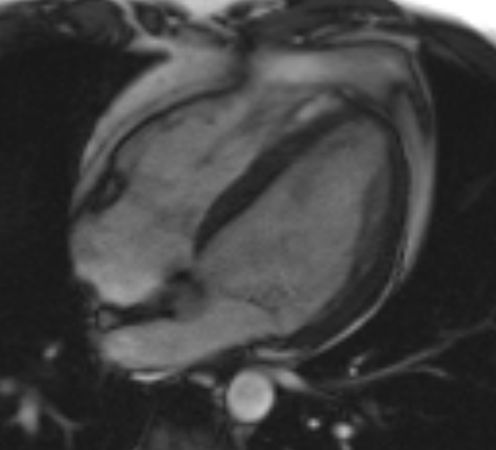

Cardio MRT

The heart examination using MRI is a central imaging technique in the clarification of heart problems. In addition to testing for a possible heart attack, this technique can also reliably detect heart attacks that have taken place. Inflammation of the heart muscle (myocarditis) or the pericardium (pericarditis) can also be ruled out with certainty by means of a heart MRI examination. In addition to these heart diseases, a large number of other heart diseases can also be diagnosed.